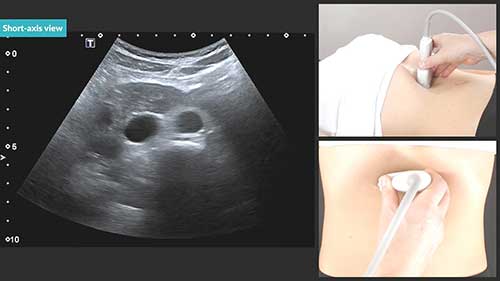

超声成像的原理